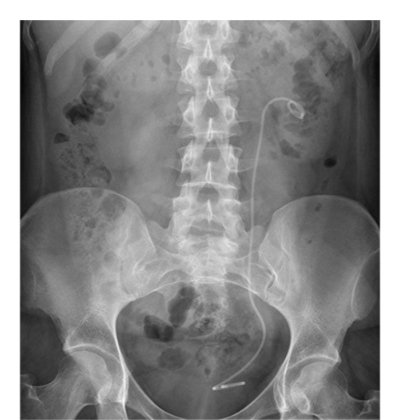

What is the cause of the abnormal calcification?

Staghorn renal calculus